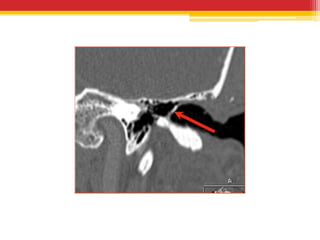

• CT temporal bones – USUALLY NOT

INDICATED, reveals unifocal or multifocal

masses or linear calcific densities in middle ear ,

epitympanum or in the tympanic membrane.